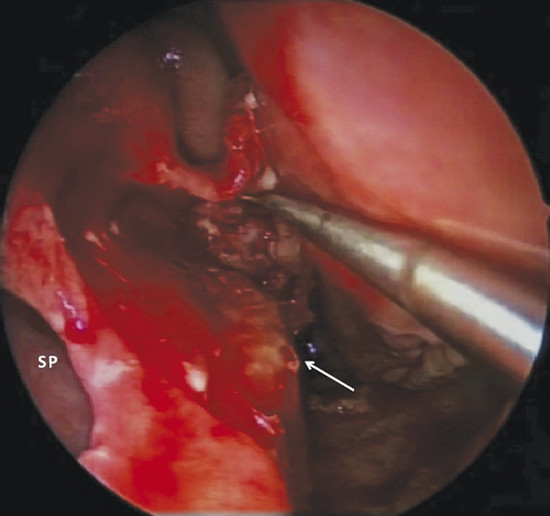

In addition, it is possible to measure the size of the NSP under endoscopic control that is critical when choosing the most suitable surgery (Fig. 6‑4).

If the defect is not circular, but oval in shape (Fig. 6‑5), it is appropriate to obtain an exact measurement of the major diameters: anteroposterior and craniocaudal, vital in choosing the most appropriate surgical technique. The vertical height of a perforation has been predicted to play a more important role in determining the surgical success than the horizontal length because the main tension between the floor of the nose and the dorsum was critical. 2 The final aspect that must be considered for surgery is the location: anterior, posterior, near the floor, or in the cranial part of the septum. Septal spurs must be identified during endoscopic examination. These should be removed during flap harvesting to get one more large and flexible mucosal layer. (Fig. 6‑6). The septum should be palpated with a sticker or with a cotton tip to discern persistent cartilage between mucosal flaps and determine whether cartilage extends close to the edges of the NSP. 2 In perforations that have occurred after septoplasty, there is usually very little cartilage left, and this makes dissection of the flaps more difficult. In this phase it is also important to check the quality of other intranasal anatomical structures, which represented potential donor sites of grafts or flaps, such as the inferior turbinate, the middle turbinate or the floor of the nasal fossa.